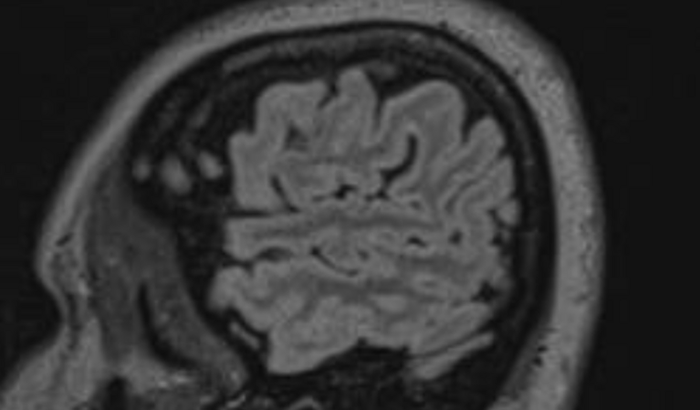

Me chamo Bruna Thatielli Borges,e através de um exame periódico na empresa em que trabalho…o médico pediu que eu procurasse um oftalmo,ok..lá fui eu ,e depois de os exames apresentarem alterações ela pediu que eu fizesse alguns mais elaborados…os quais apresentaram resultados mais alterados,ela então pediu duas ressonâncias para descartar algumas doenças piores…doencas descartadas,chegou-se no pseudotumor cerebral…que é uma doenca que caracteriza a pressão intracraniana elevada,causando inchaço no nervo óptico danificando a visão ,causando crises de dores de cabeça intensas…e gerando acúmulo de liquor na caixa craniana,tendo que realizar várias punções lombares para drenar esse liquido.Por agora preciso muito de ajuda para pagar esses exames de emergência os quais ainda obtive um grande desconto pois fiz pelo sindicato ao qual sou afiliada.Agradeço toda ajuda que receber…E que Deus nos abençoe sempre.